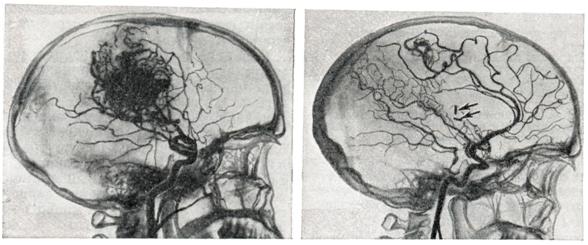

Рис. 1.

Мешковидная аневризма правой внутренней сонной артерии (ангиограммы): а — до операции; видна шейка (указана стрелкой) и тело аневризмы; б — ангиограмма после операции; виден клипс на шейке аневризмы (указан стрелкой); аневризма не выполняется.